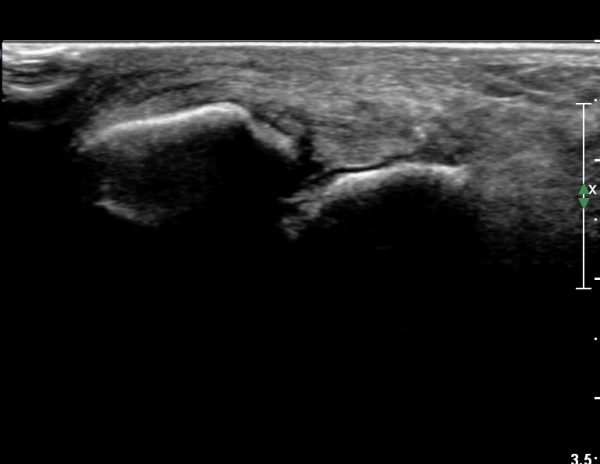

Àü¹æ¸»´ÜÁ¾°ñºñ°ñÀδë Á¾´Ü¸é°Ë»ç¿¡¼­ ƯÀÌ ¼Ò°ßÀ» º¸ÀÌÁö ¾ÊÀ½(»çÁø 1).